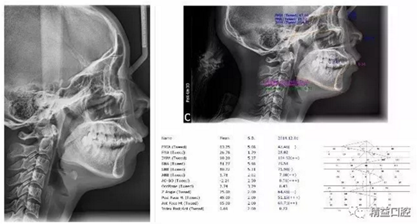

矯正前頭顱側(cè)位片

嘴唇突度非常明顯,后期經(jīng)過測量,發(fā)現(xiàn)是典型的安氏II類加骨性II類,齙牙前突。